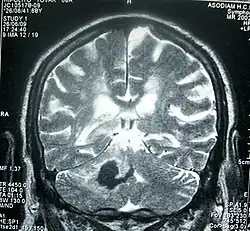

Perinatal stroke can be diagnosed with medical imaging techniques that present the brain's image. The usage of diffusion-weighted imaging with magnetic resonance imaging is effective for early diagnosis of perinatal stroke.[18] Computerized tomography (CT) is also a commonly used diagnostic technique for this disease.[35] These medical imaging techniques can show bleeding or blockage in the brain and detect damage caused by ischemic stroke or hemorrhages to the brain tissues.[36] Magnetic resonance imaging is clinically preferred to computerized tomography as it can highlight the brain's blood flow.[35] In addition, perinatal stroke is challenging to classify on computerized tomography as the neonatal brain has higher water content.[7][36] However, in certain situations, such as the inability to transport unstable infants with severe respiratory or cardiac disorders from the intensive care unit, cranial ultrasound is used as an alternative to magnetic resonance imaging.[7] Cranial ultrasound can identify intracranial hemorrhage, intraventricular hemorrhage, and large cerebral sinus venous thrombosis along with the brain's blood flow.[7]